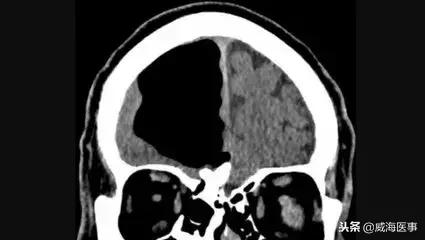

王先生的病变部位解剖结构复杂,周围神经、颈内动脉等结构受肿瘤所累,而且肿瘤已经累及颅内。“他的恶性肿瘤就长在了鼻腔最上方的颅底部位,这是个死角,必须借助仪器导航才能‘下手’。”李吉洲说

“我得感谢这套宝贝,没有它我们也不敢‘下手’。”李吉洲说的“宝贝”是一套名为美敦力FUSION电磁导航手术系统的仪器,这是威海市的第一台也是唯一一台,正是它的指引,李吉洲才精准无误地找到恶性肿瘤并切除。

网络配图